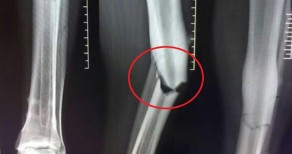

Lig maçında bacağı kırılan Demba Ba'nın sahalara dönmesi 2.5 yılı bulacak. 31 yaşındaki futbolcunun futbola veda etmesine kesin gözüyle bakılıyor.

Çin Ligi'nde Shangai Shenhua'nın lig maçında bacağı kırılan Beşiktaş'ın eski yıldızı Demba Ba'nın futbol hayatı bitebilir...

Senegalli futbolcunun ilk kontrollerini yapan ortopedi uzmanı Guwang-wu, 'Araba kazasıyla eşdeğerde bir sakatlık durumu var.

Demba Ba'nın iyileşmesi 1-1.5 yılı bulabilir. Sahalara dönme süresi de 2.5 yılı... İlk ameliyat sonrası 4 ay geçecek ve ikinci bir ameliyata girecek. Bu da en az 1 yıl alır' dedi.